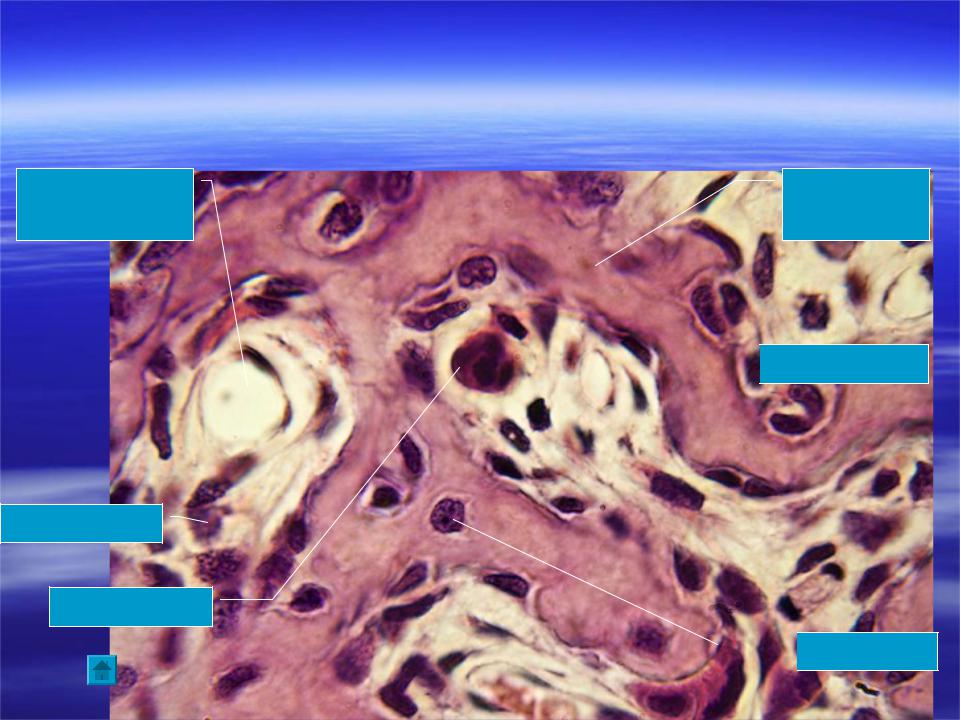

Структура грубоволокнистой костной ткани: наглядные примеры